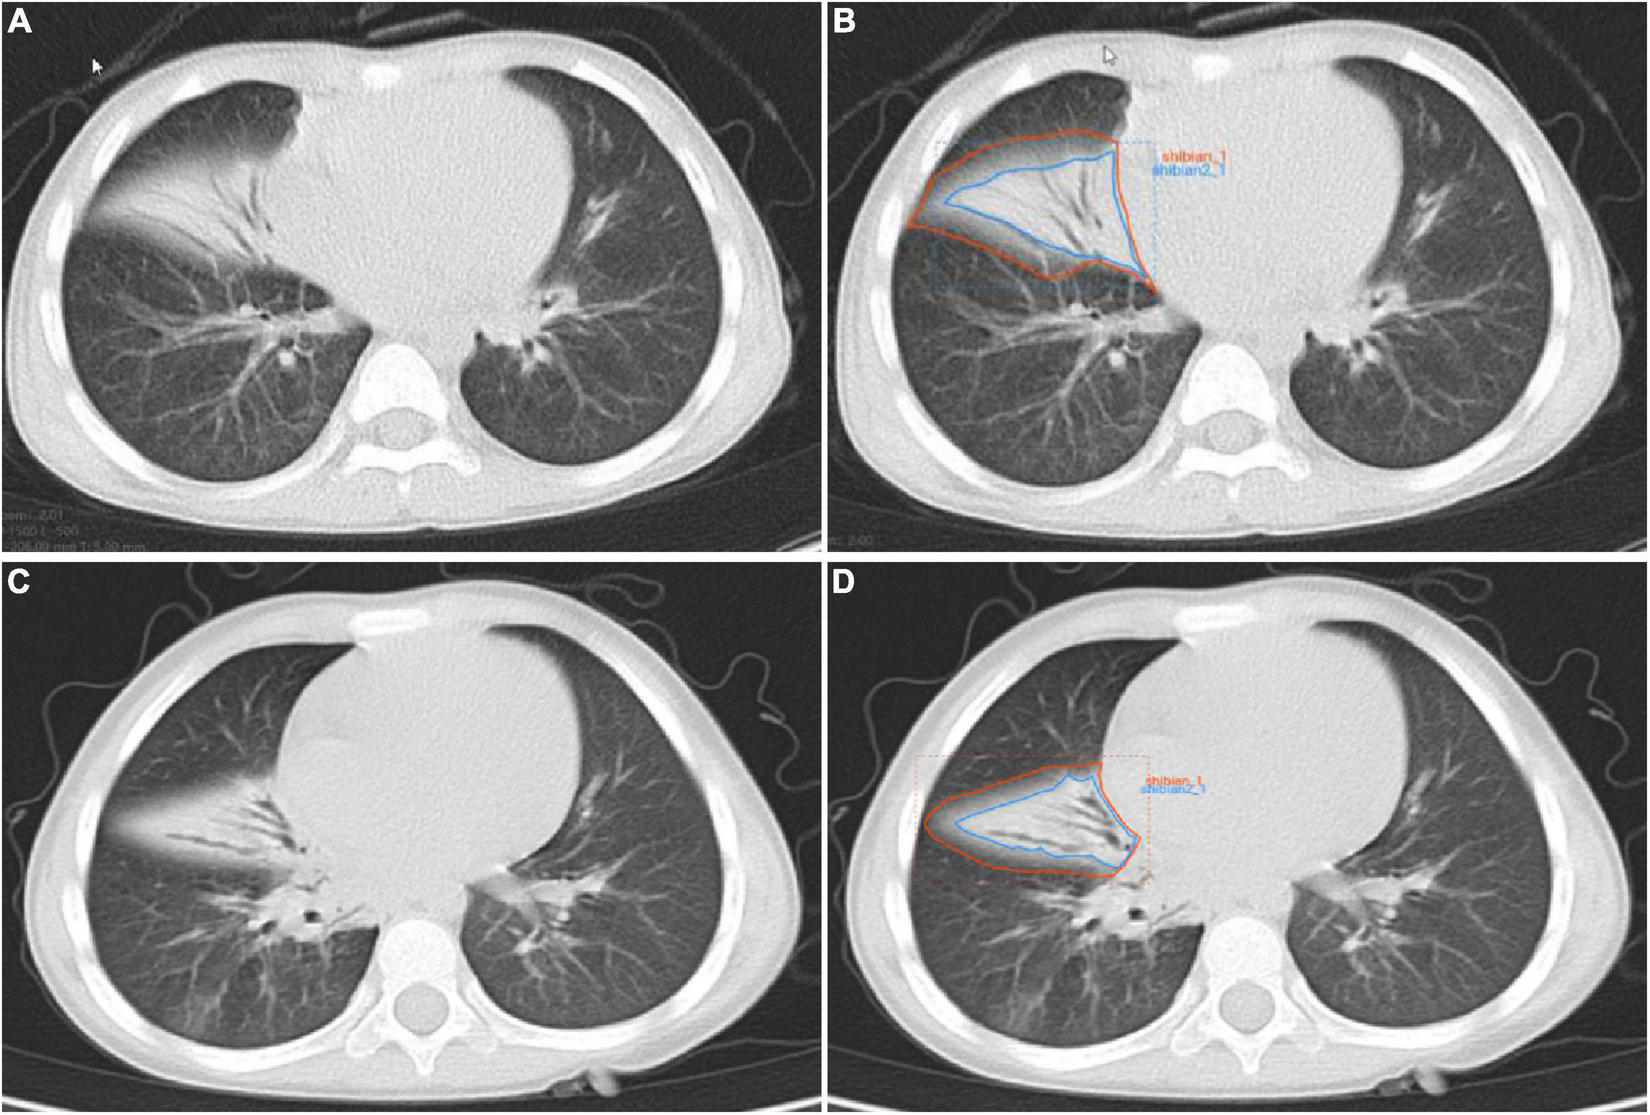

The flow-chart depicting image of feature extraction and selection and model construction is presented in Figure 1. The ROIs of the lesions on all lung window CT images were assessed and delineated in a double-blind manner by two radiologists with 5 and 10 years of experience, respectively, and following review was performed by a senior physician. If the difference was ≥5%, the latter would determine the boundary and redraw it. Two different kinds of ROI delineation of the lesion were made (Figures 2A–D): the first included the single consolidation part of the lesion (Figures 2B,D, blue line) and the second included the consolidation and surrounding halo area (Figures 2B,D, orange line). Meanwhile, the mediastinal window images was also used for the judgment of consolidation part of the lesion as the reference. The cavity, necrosis, hemorrhage or ground glassin oppacities in lesion were also included in the ROI. At the same time, the adjacent mediastinum, thickening pleura, and pleural effusion were avoided to draw by referring to these structures on mediastinal window CT. Grayscale normalization was then performed to reduce the impact of contrast and brightness changes. Ultimately, 102 ROIs were segmented from CT images of 102 patients and used for subject analysis.

FIGURE 2

Manual delineation on lung window CT images in a 25-month female patient with mycoplasma pneumoniae pneumonia (A,B) and a 21-month male patient with streptococcus pneumoniae pneumonia (C,D). CT shows the similar appearances with consolidation and surrounding halo in middle lobe of right lung (A,C), and two ROIs (blue line and orange line) are delineated in each patient.